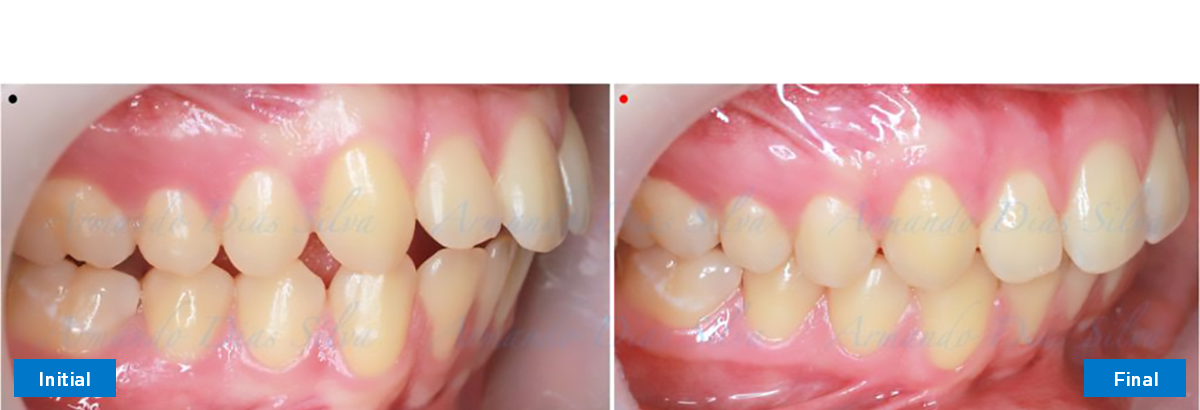

Clase II, Div. 1: Protrusión del incisivo central y espacios anteriores (SureSmile® Aligners)

Principal queja del paciente: Protrusión del incisivo central y mordida abierta. El paciente rechaza la expansión del arco palatino (MARPE) y las extracciones.

Este paciente adolescente presenta molares de Clase II y no le gusta su mordida abierta ni lo protrusivos que son sus dientes frontales. Por sus fotografías faciales, parece que su mandíbula es retrognática o le falta volumen en la barbilla. El historial del paciente también indica que existe un problema funcional al no haber guía de los incisivos.

• Molares de clase I logrados con distalización y sin elásticos